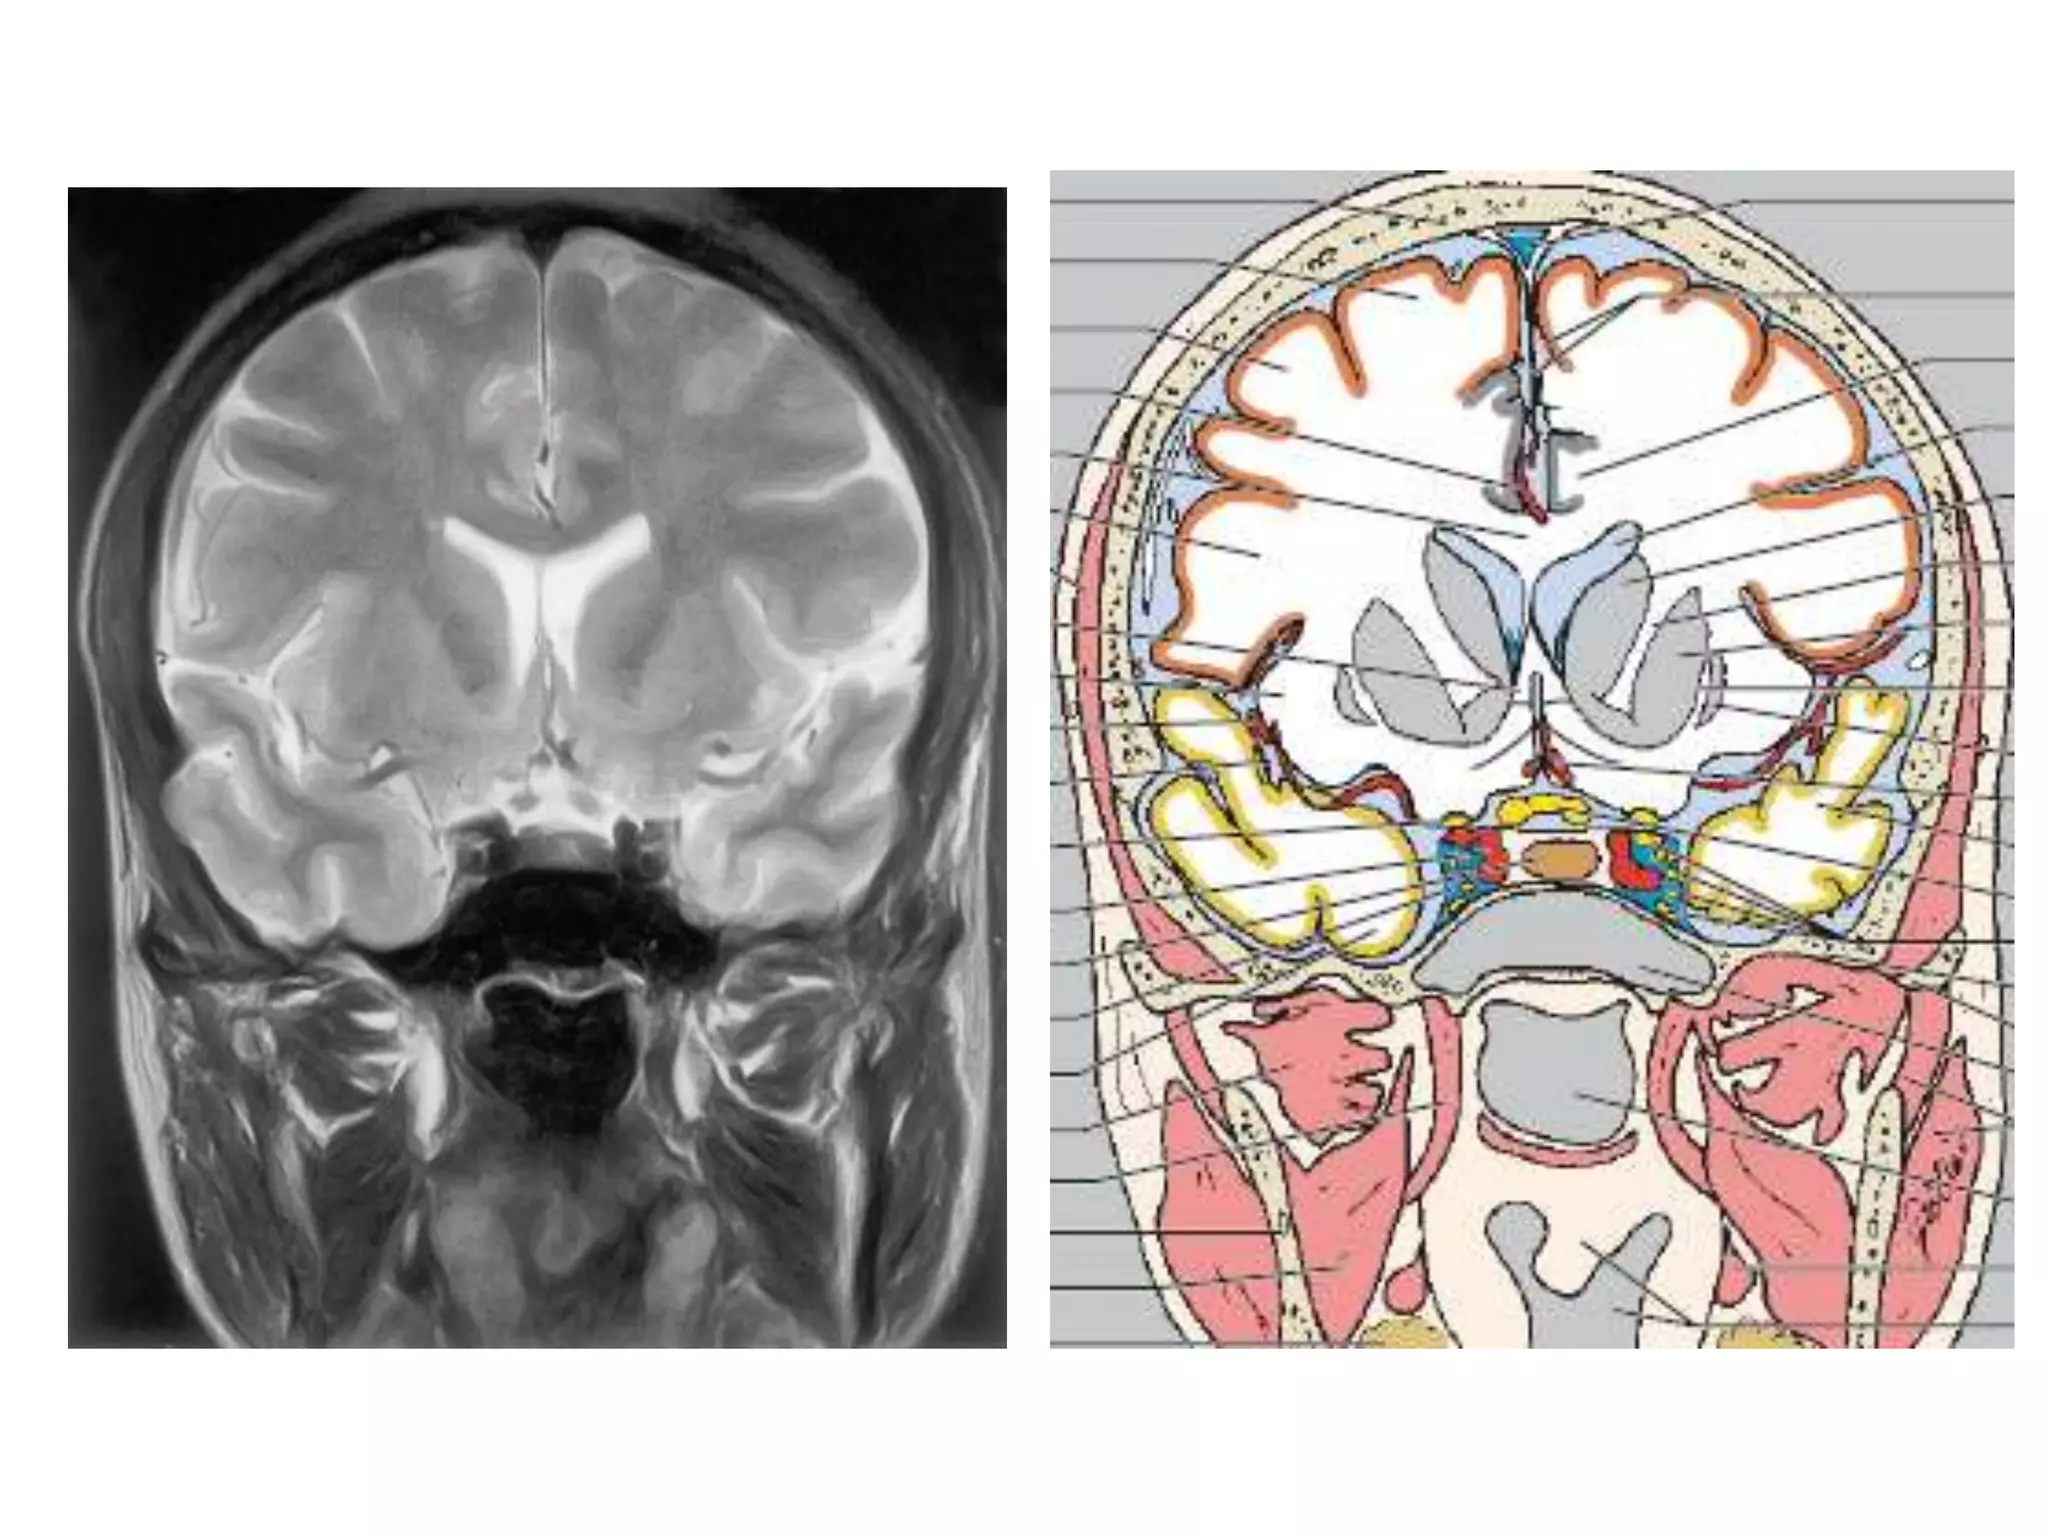

Coronal : frontal horns – inverted triangle

body – flattened

temporal horns – like ‘C’ on its sides.

4TH VENTRICLE

• 4 angles - rostral, caudal , two lat.

• Relations - antr.

postr.

lateral

inferior

• Communications

supr. and infr.

postero infr.

postero lat.

Radiology

• Axial MRI / CT – ‘kidney bean’ turned on its side.

• Saggital MRI - mid point of line drawn b/w T. sella

and trocula should intersect middle of 4th

ventricle.

• Coronal MRI – elongated rhomboid shape

CISTERNS